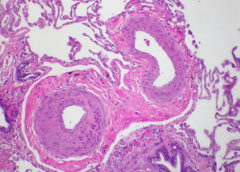

La 29esima edizione del congresso ERS che si è svolto a Madrid tra il 28 settembre e il 2 ottobre è stata l’occasione per fare un punto sull’ipertensione polmonare. Cosa sappiamo di questa rara malattia delle arterie polmonari? Quali trattamenti sono disponibili? Sono davvero…

(Reuters Health) – Secondo i risultati di uno studio osservazionale, pubblicati da Lancet Respiratory Medicine, un gruppo di 9 proteine plasmatiche può identificare i pazienti con ipertensione arteriosa polmonare (PAH) che hanno un rischio più elevato di mortalità. Lo studio La sopravvivenza dei pazienti…

(Reuters Health) – I pazienti che ricevono una endoarteriectomia polmonare (PEA) come trattamento per l’ipertensione polmonare tromboembolitica cronica (CTEPH) vivono meglio nel lungo termine rispetto a quelli che ricevono un trattamento farmacologico. È quanto emerge dall’analisi deirisultati di un registro internazionale. La CTEPH può essere…